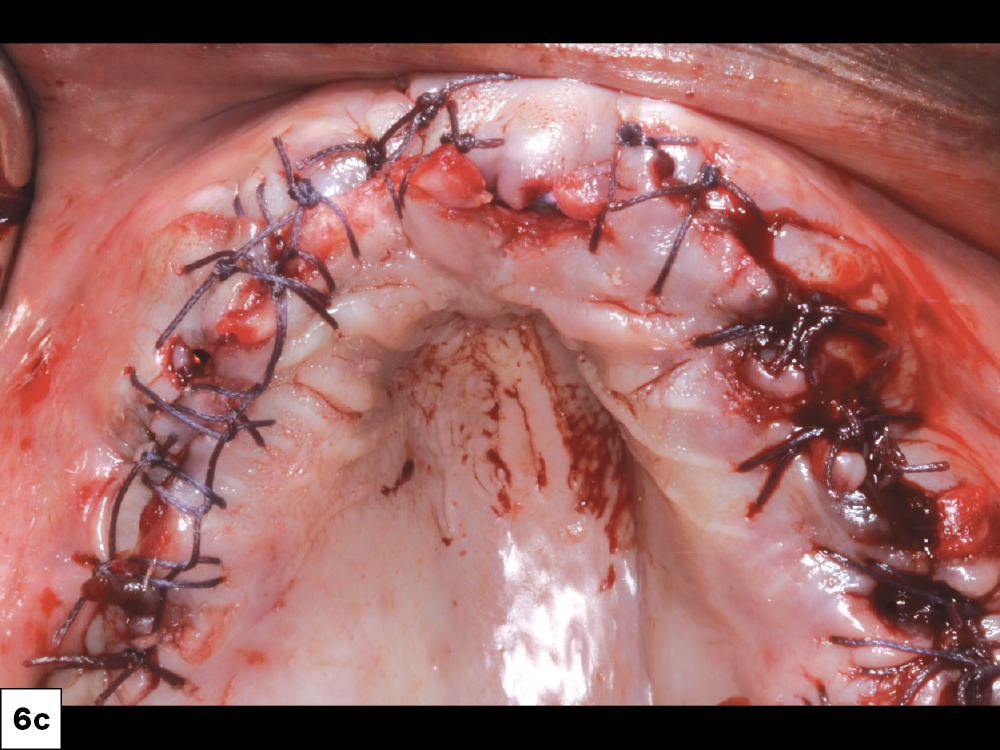

Figures 6a–6c: I used Newport Biologics allograft particulate (Glidewell Direct; Irvine, Calif.) to fill in facial defects and socket sites to prevent the invagination of epithelium.  We used a platelet-rich fibrin membrane to promote healing and bone regeneration. I closed the flap with continuous REDISORB PRO® sutures (available through Glidewell Direct).